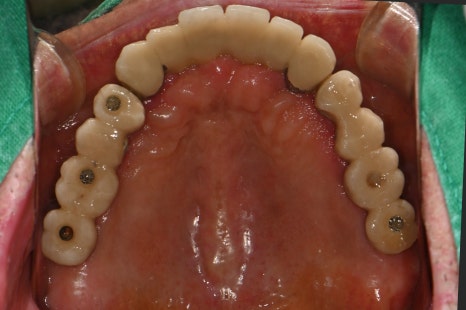

Left photo: Most of the upper teeth had implant prostheses, but the screw access holes were open and needed repair.

Left photo: The upper prosthesis had good overall fixation and the bite was designed to be stable.